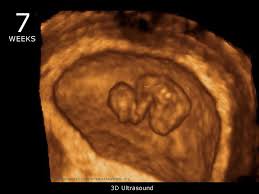

Embryo size your baby is about the size of a blueberry during week 7. Baby development at 7 weeks. 0 31 in 0 79 cm weight. The embryo has distinct slightly webbed.

Your baby s stomach and esophagus start to form. At 7 weeks pregnant your baby is the size of a blueberry. At the beginning of the 7th week the embryo which is around 0 16 inches big grows to a size of 0 52 inches at the end of the 7th week. Your baby is about the size of a blueberry your baby has doubled in size since last week and is now about 1 2 inch long.

Morning sickness swollen breasts and food aversions are some common symptoms at 7 weeks. The esophagus is the tube that moves food from your baby s mouth to his stomach. 0 02 oz 0 5 g embryo image week 7. Your embryo measures about 51 inches having doubled in size since last week.